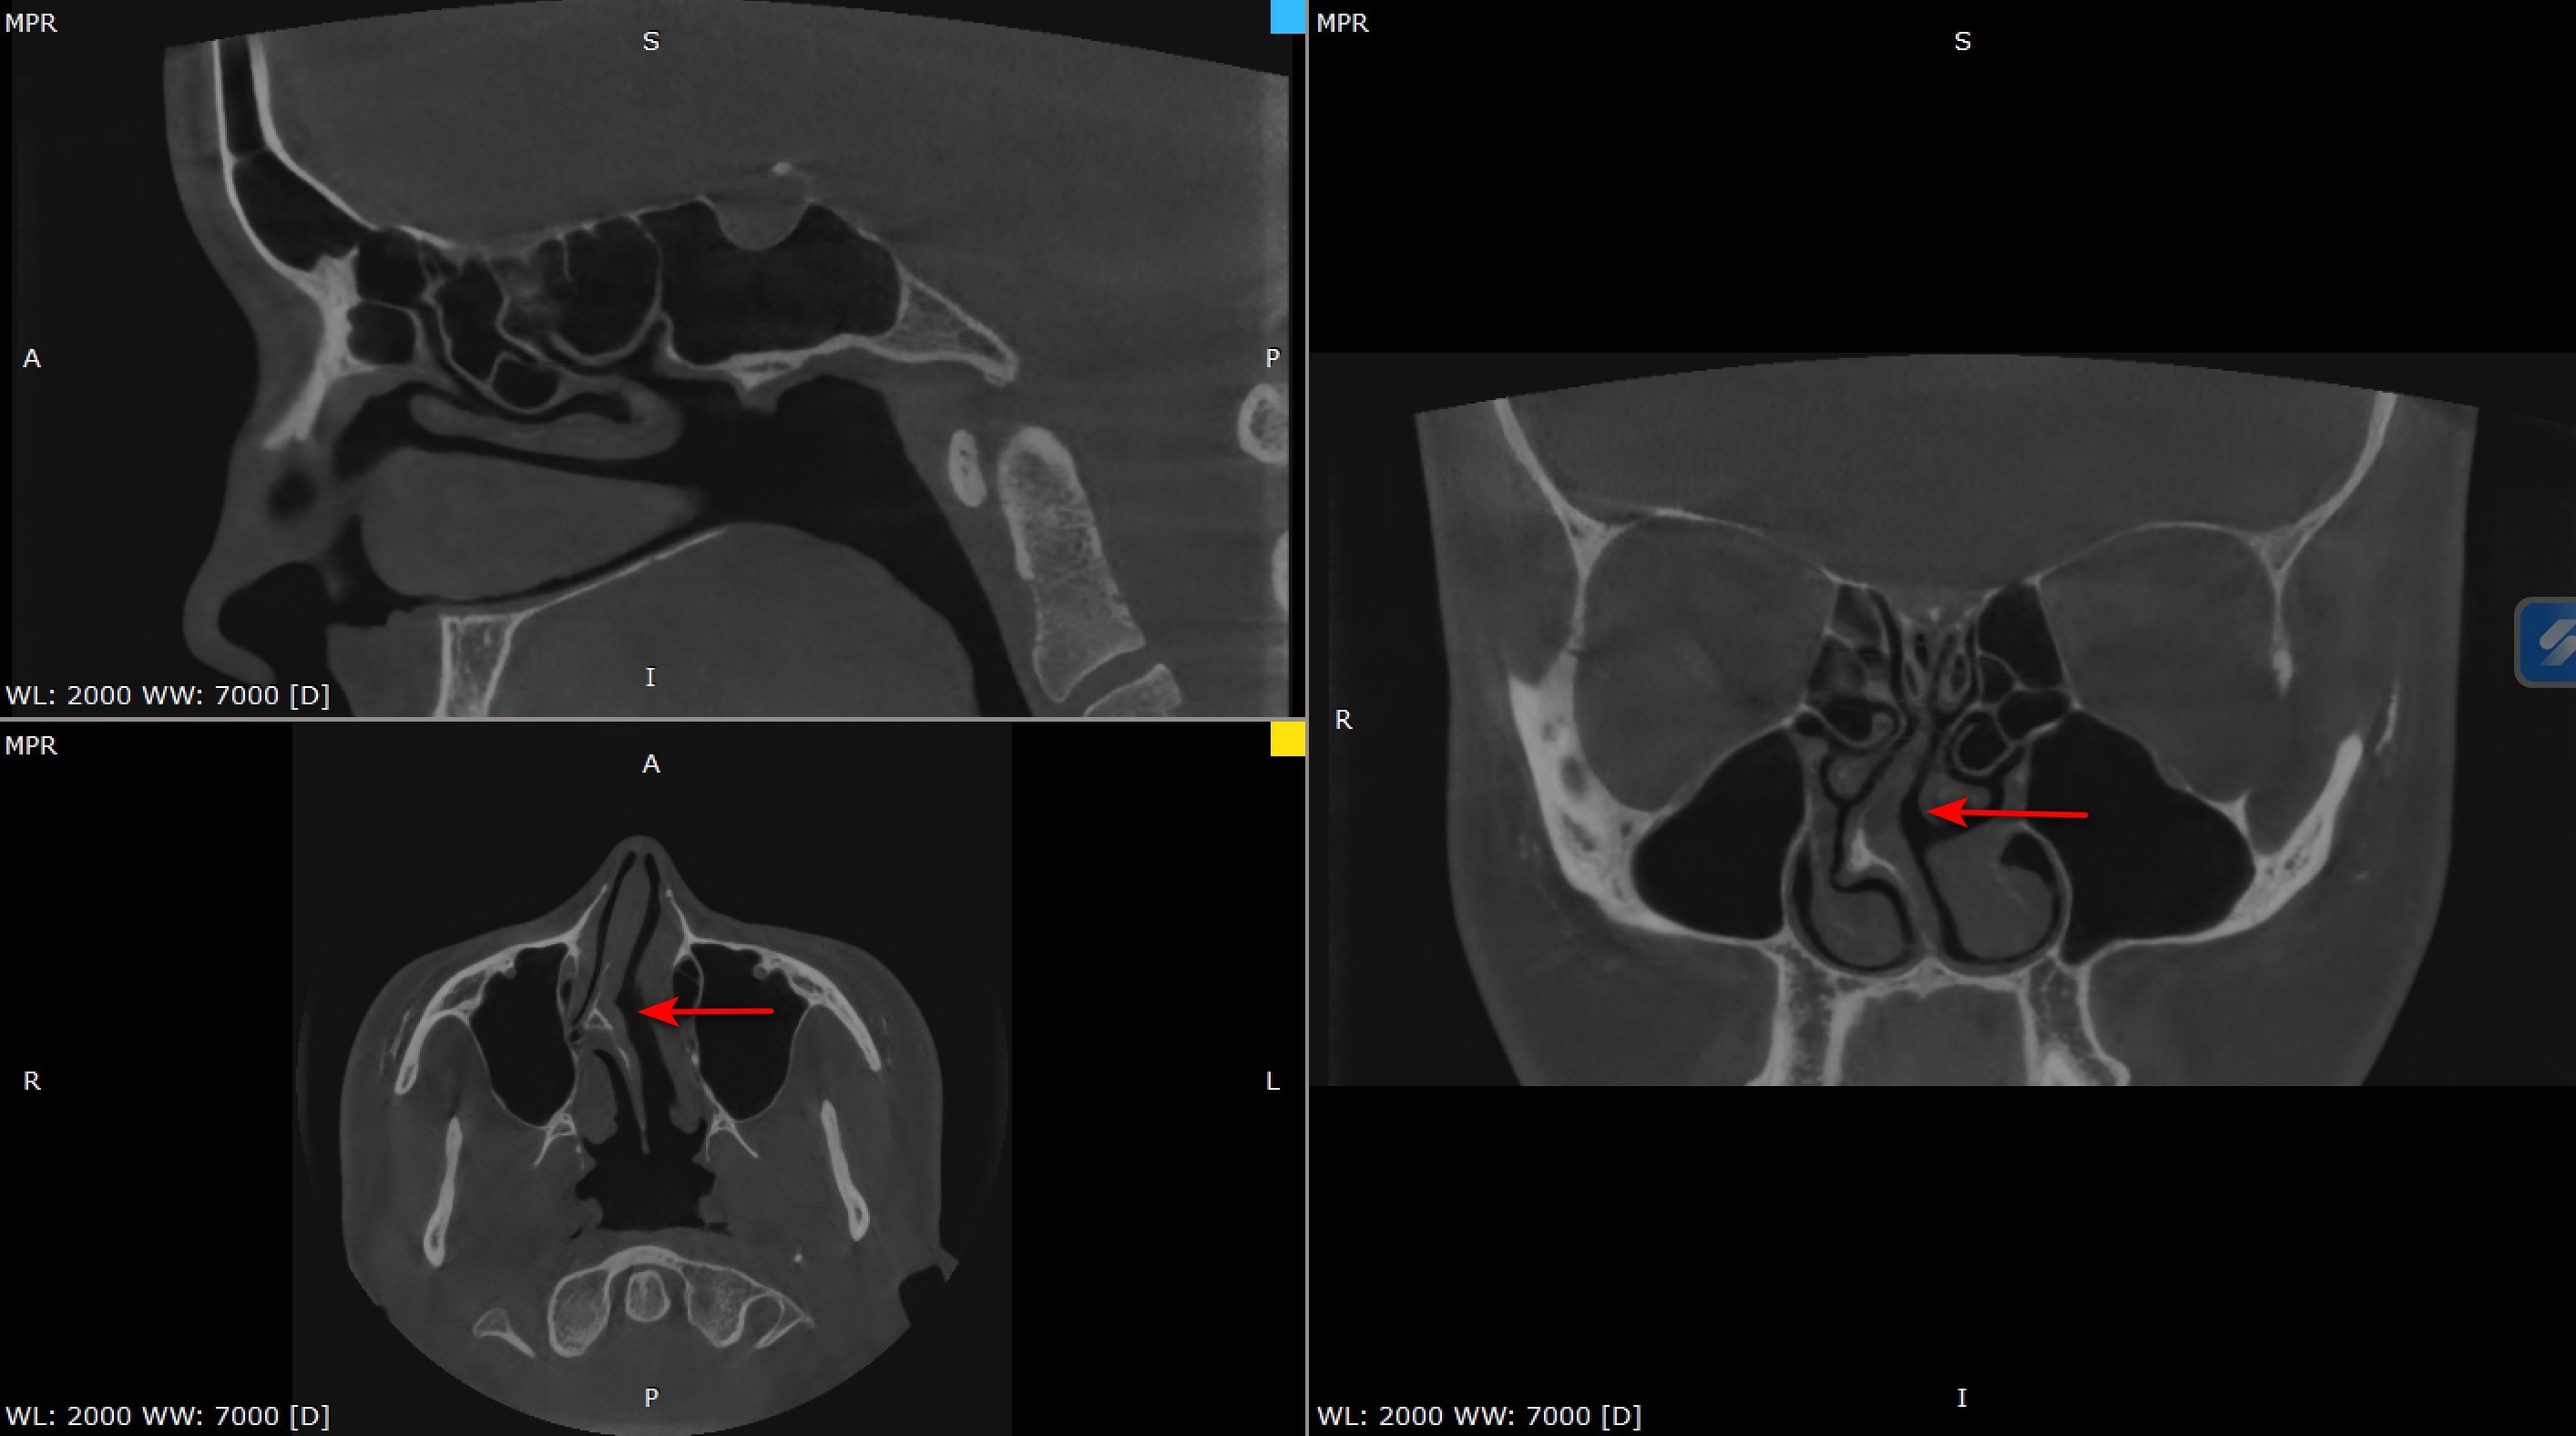

- ендоскопія носа

- КТ приносових пазух